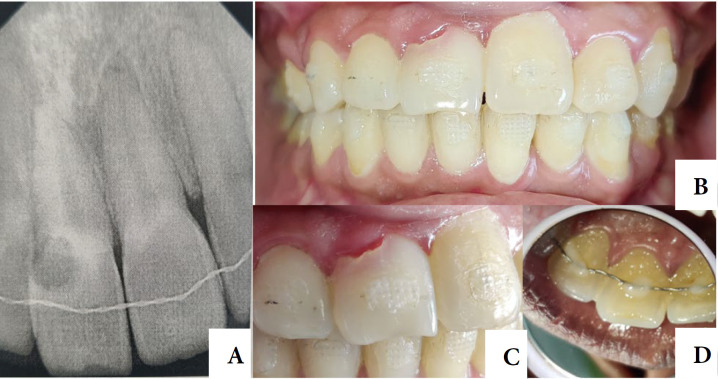

Internal tooth resorption is a subtle proceeding typically occurring in teeth with a history of trauma, chronic pulpal inflammation, or caries-related issues. It is frequently observed in anterior teeth that are more vulnerable and susceptible to injury, but can also affect posterior teeth, often due to pulp involvement in caries. This case report illustrates the handling of a resorption in the cervical third of the root. A 28-year-old female patient was referred for endodontic and esthetic treatment for her primary complaint of pink spot staining in her upper left central incisor's crown. The tooth had symptomatic apical periodontitis. Final Diagnosis was Class 4 invasive cervical resorption. This case study outlines the effective management of an extensive internal root resorption using a non-surgical approach and the application of MTA as repairing material with thermo-plascticized gutta-percha as an obturation material. The treatment resulted in the resolution of symptoms and the restoration of periapical tissues. Timely detection, addressing the underlying cause, and effective care of the invasive cervical resorption are essential for achieving a favorable treatment outcome. Obtaining positive results required a patient-centered approach, well-planned therapy, and an accurate diagnosis.